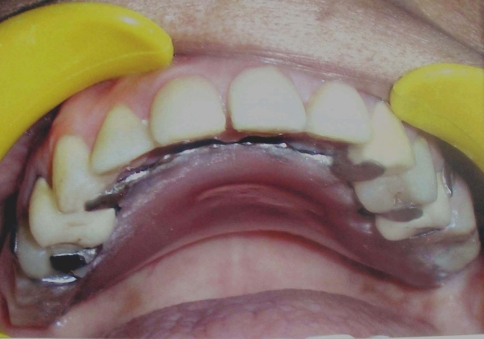

Oral examination showed multiple grossly decayed teeth and reduced vertical dimension of occlusion with 7 mm free way space (Fig. 1). Teeth # 17, 26, 27, 36, 46 were missing and teeth # 16, 45, 47 were extracted because of periapical pathologies and extensive coronal structure loss [9]. Routine endodontic treatment of teeth with carious exposures (# 14, 23, 25, 31, 32, 34, 35, 37, 41, 42, 43, 44) was done followed by post and core build up (C-Post, Bisco Inc, Schamburg, Illinosis) in teeth # 14, 31, 32, 34, 35, 37, 41, 42, 43, 44 as most of their coronal tooth structure was destroyed [10]. Teeth # 23, 25, 33 required core restorations with composite resin (Filtek Z250, 3M ESPE, St. Paul, Minnesota). Teeth with minor carious involvement (# 13, 12, 11, 21, 22) were restored with light cured Glass ionomer cement (Fuji LC GC, Alsip, Illinosis).

Fig. 1.

Pre-operative intraoral view